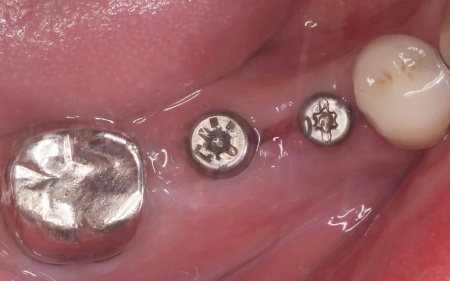

そこで歯ぐきの一部を開き内部を直接確認したところ、いずれの歯根が垂直方向に割れていました。

歯根が割れている場合、細菌感染が進行して歯ぐきの炎症が広がったり周囲の歯やあごの骨にまで影響を及ぼしたりする可能性があります。

以上のことから、歯を温存することは難しいため抜歯が必要と診断しました。